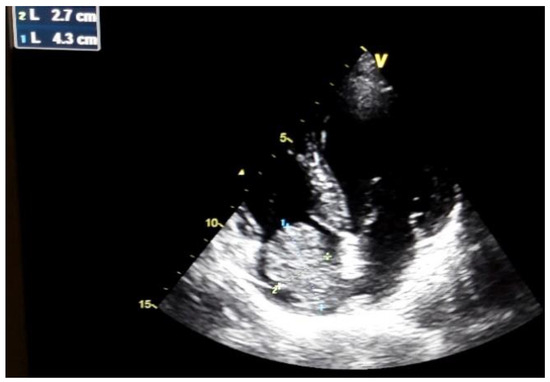

Hepatocarcinoma with Tumor Thrombus Occupying the Right Atrium and Portal Vein in a Patient with Hereditary Hemochromatosis and Liver Cirrhosis

Case report